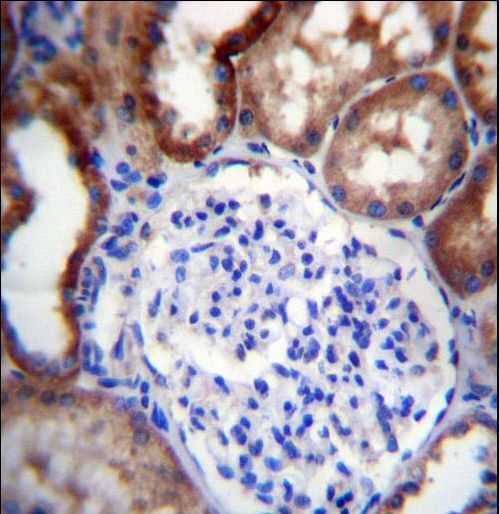

- Experimental details

- LINGO4 Antibody immunohistochemistry of formalin-fixed and paraffin-embedded human kidney tissue followed by peroxidase-conjugated secondary antibody and DAB staining.